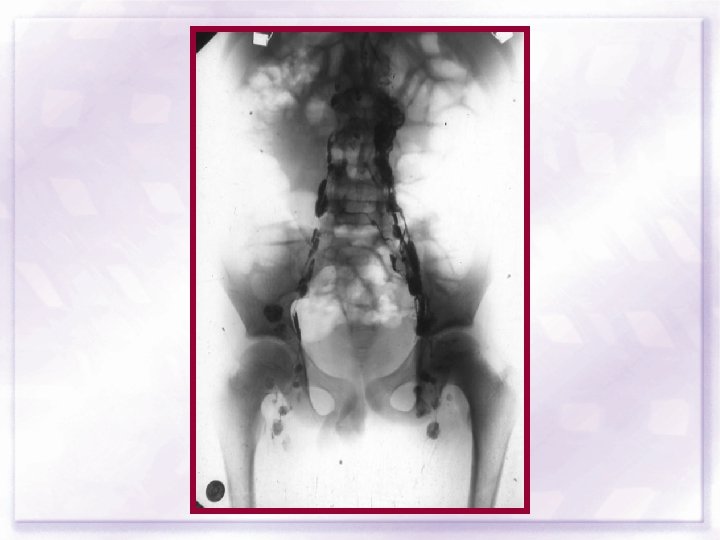

Tanı Çalışmaları • • • Ayrıntılı öylü ve FM TKS, biyokimya ESR Lenf nodu biyopsisi PA akc grafisi Boyun-Toraks-Abdomen-Pelvik CT Lenfanjiyogram ? ? ? Kİ biyopsisi Kemik sintigrafisi Ga 67 ile vücut sintigrafisi Cerrahi evreleme ? ? ?

SPLENEKTOMİ LENF NODU BİYOPSİLERİ KARACİĞER BİYOPSİSİ kama iğne biyopsisi KEMİK İLİĞİ kama biyopsi peri - portal splenik hilum çölyak aks para - aortik bifurkasyon ortak iliak mezenterik